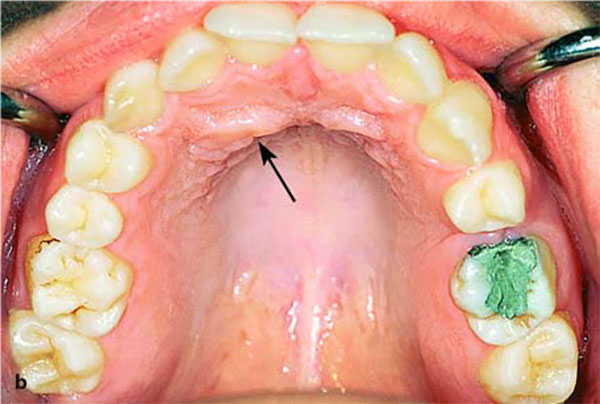

نهفتگی یک طرفه در لبیال